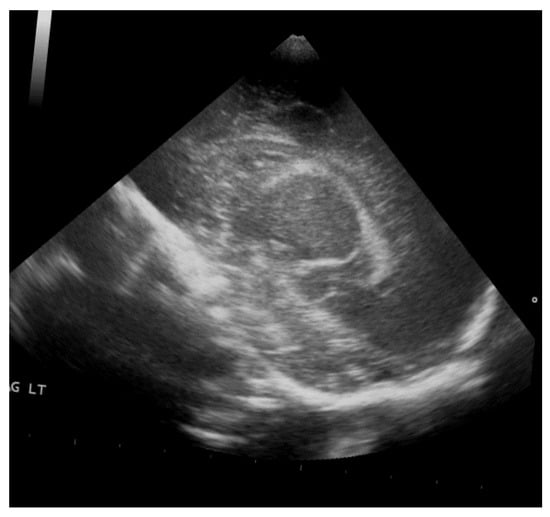

To address preprocessing, we applied cropping to automatically center and focus on the region of interest (ROI) in each image, as shown in Figure 5. This step removed irrelevant background and emphasized the critical areas where hemorrhages were most likely to appear. We followed this by resizing all images to a uniform size of 255 × 255 pixels to ensure consistency across the dataset, allowing the model to process the images efficiently while maintaining sufficient resolution for identifying fine details in the ultrasound scans.

Figure 5.

Rotation by 10%.

Accurate annotation was performed using Roboflow, with bounding boxes manually drawn around hemorrhagic areas under the guidance and supervision of KFHU doctors. Different colors were assigned to represent each hemorrhage grade (g1, g2, g3, g4) and the Normal class, ensuring the model could effectively distinguish between them. This meticulous annotation process allowed the YOLOv8 model to focus on the most relevant areas, significantly enhancing its functionality. For instance, Figure 6 illustrates an orange box marking a Grade 3 hemorrhage, a red box for Grade 4, a purple box for Grade 1, a green box for Grade 2, and a yellow-green box for Normal class. Together, these preprocessing and augmentation techniques played a critical role in enhancing the quality and diversity of the dataset, which in turn improved the model’s performance in detecting and classifying GMH across various grades.

Figure 6.

Cropped ROI.